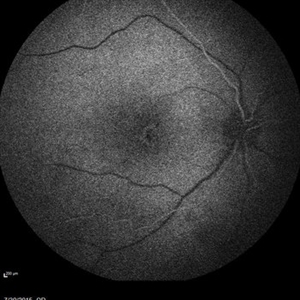

Retinal Dystrophy of 24-Year-Old Male/ Red Free OS

Nov 25 2015 by Zach Dupureur

Fluorescein angiography of a 24-year-old male. Juvenile retinoschisis on OCT. FA shows outer retinal staining. Could be associated with Goldman Farve Syndrome.

Photographer: Zach Dupureur OCT-C

Imaging device: Heidelberg Spectralis

Condition/keywords: Goldmann-Favre Syndrome, juvenile retinoschisis, retinal dystrophy